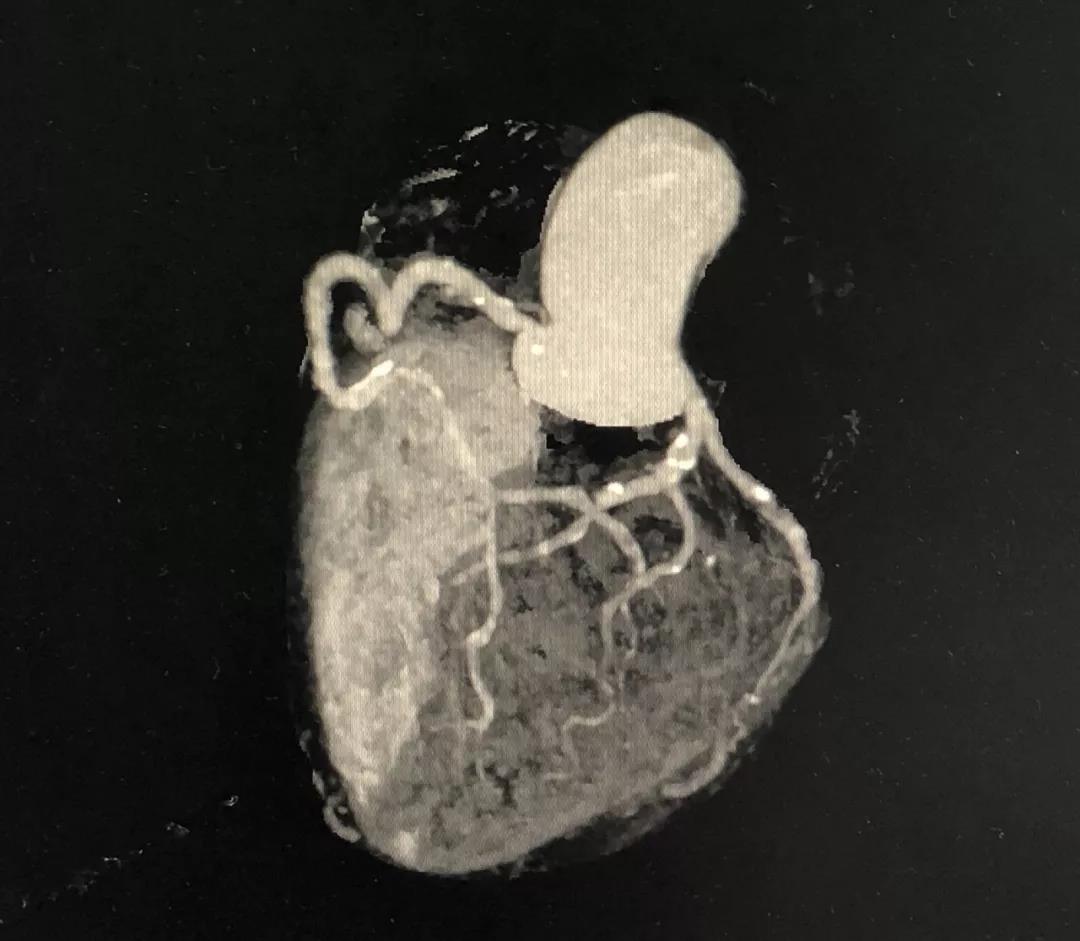

冠状动脉CTA

CCTA LAD病变特点:

近段血管较直

中远段血管偏细

中远段血管病变弥漫

病变段扭曲不很明显

病变段无重要分支发出

病变血管段有局灶点状钙化

CCTA LCX病变特点:

LM前分叉正常

LCX相对较直

中段病变伴局灶点状钙化